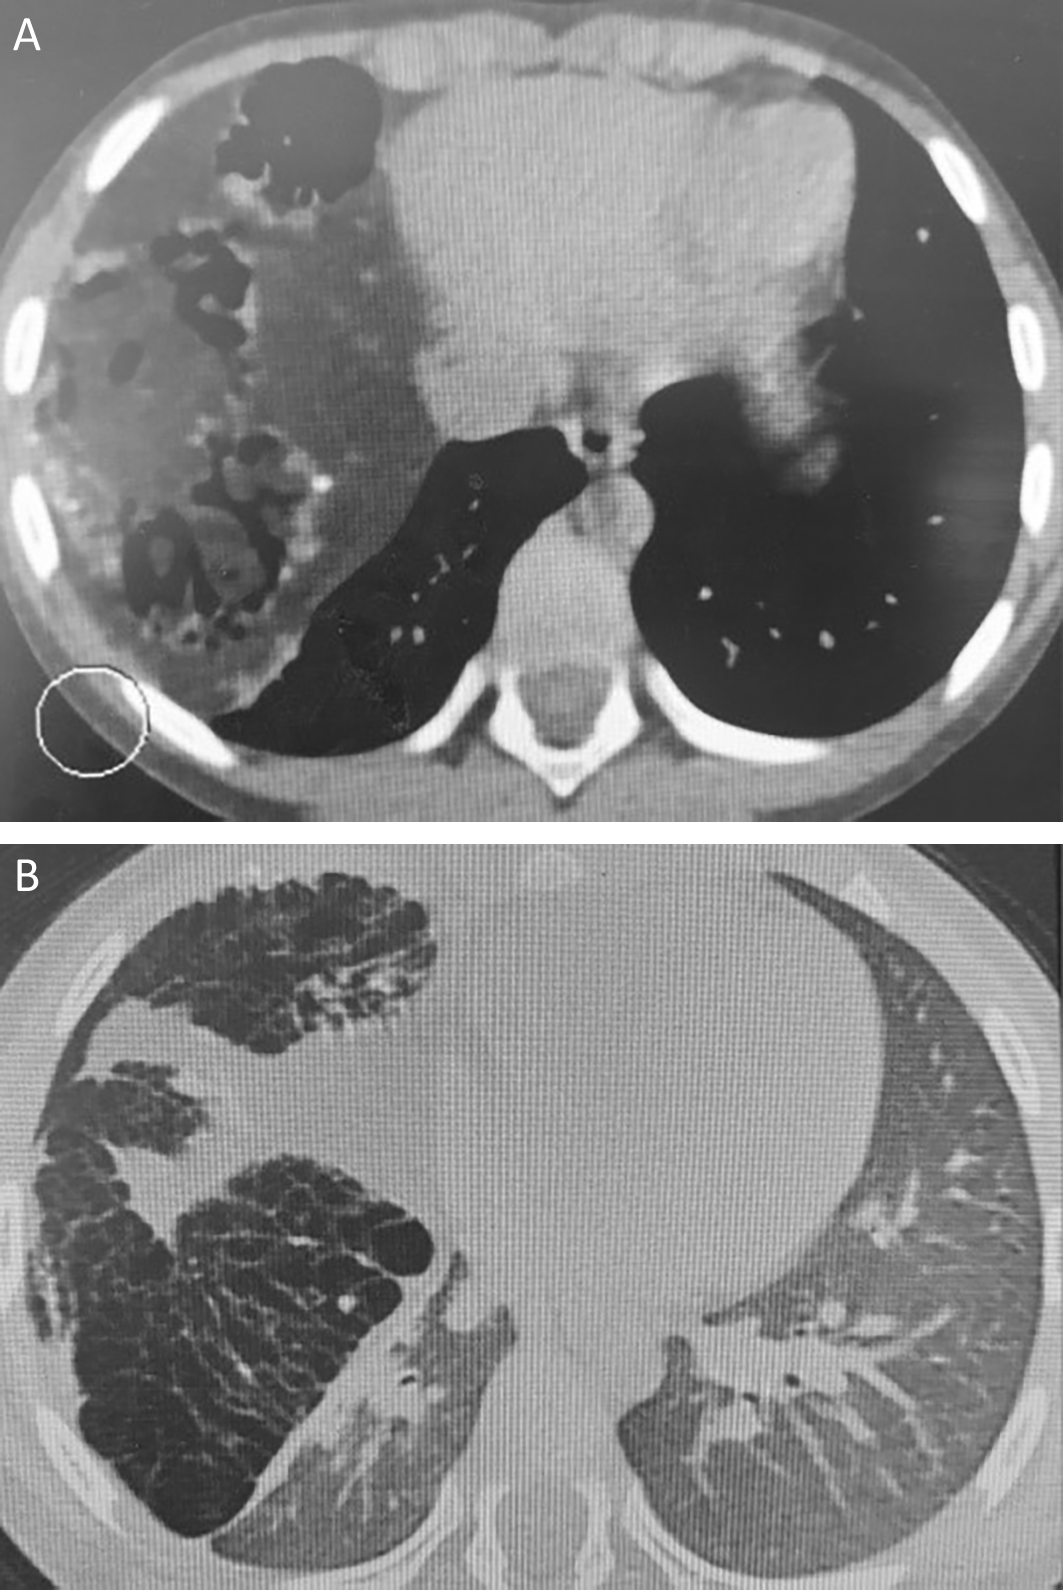

Chest computed tomography revealed a giant cystic and solid mass measuring 122 × 80 × 102 mm compressing the right middle and lower lobes. This mass contained tissular, fatty, and calcified elements, along with multiple airy cysts, suggesting a giant pulmonary hamartoma (Figure 2).

On tomodensitometry, lung hamartoma usually appears as a lobulated nodule with a heterogeneous density and no pleural traction. Characteristic imaging manifestations include the presence of fat (60% of the cases) and a popcorn appearance of calcifications observed in 5-50% of the cases.10 Malignant transformation is exceedingly rare.11